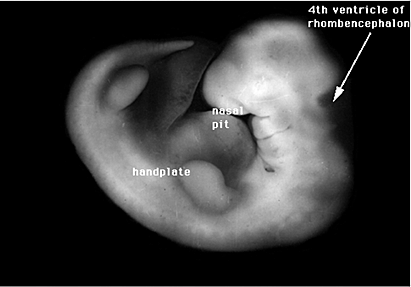

Es posible distinguir en la cabeza el esbozo de los ojos y de los oídos, la hendidura bucal se divide en 2 para dar lugar a la boca y las fosas nasales, comienza la formación de los pulmones, los brazos y las piernas se han alargado y se pueden distinguir las áreas de los pies y de las manos.

La diferenciación celular se desarrolla en 5 áreas y algunos nervios craneales se hacen visibles. Los esbozos de los miembros son claros,especialmente los de los brazos. Se comienza la estructura de la nariz, aunque no es posible identificar ningún rasgo facial.

La diferenciación celular se desarrolla en 5 áreas y algunos nervios craneales se hacen visibles. Los esbozos de los miembros son claros, especialmente los de los brazos. Se comienza la estructura de la nariz, aunque no es posible identificar ningún rasgo facial.